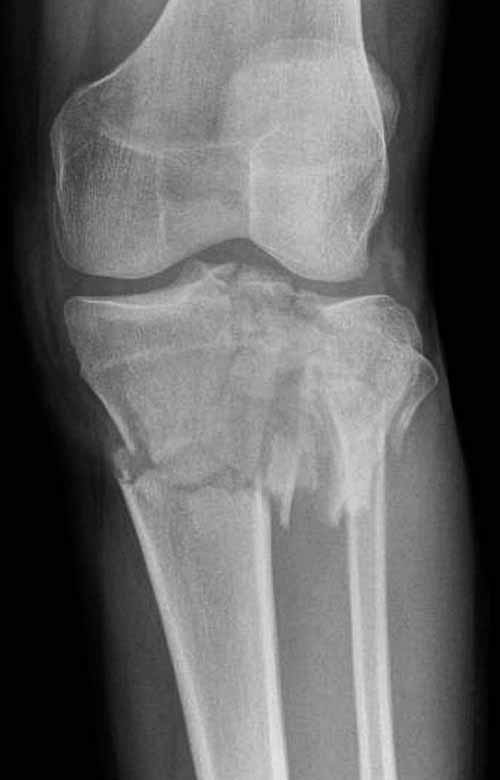

Двухколоннный перелом тибиал плато с вовлечением проксимального диафиза. Внутрисуставной компонент без смещения, и такой перелом можно лечить любым из описанных методов, о которых говорят наши коллеги.

Удобно аппаратом Илизарова или интрамедуллярным гвоздем. Гвозди не так сложно, как пугают, тем более Александр готов помощь с методичкой. Сперва надо установить компрессирующие шурупы на мыщелки. Давно отказались в пользу 3.5-4.0 мм кортикальных вместо толстых спонгиозных, потому что не доказаны преимущества толстых шурупов. Тонкие шурупы в субхондральной зоне смотрятся намного элегантнее, чем толстые 6.5.

Это мероприятие превращает перелом в простой диафизарный, который легко можно фиксировать гвоздем. Шурупы надо установить сзади предполагаемого места введения гвоздя.

В приложении этапы фиксации Both Column Fx и пластиной Synthes для плеча при переломе медиального мыщелка.